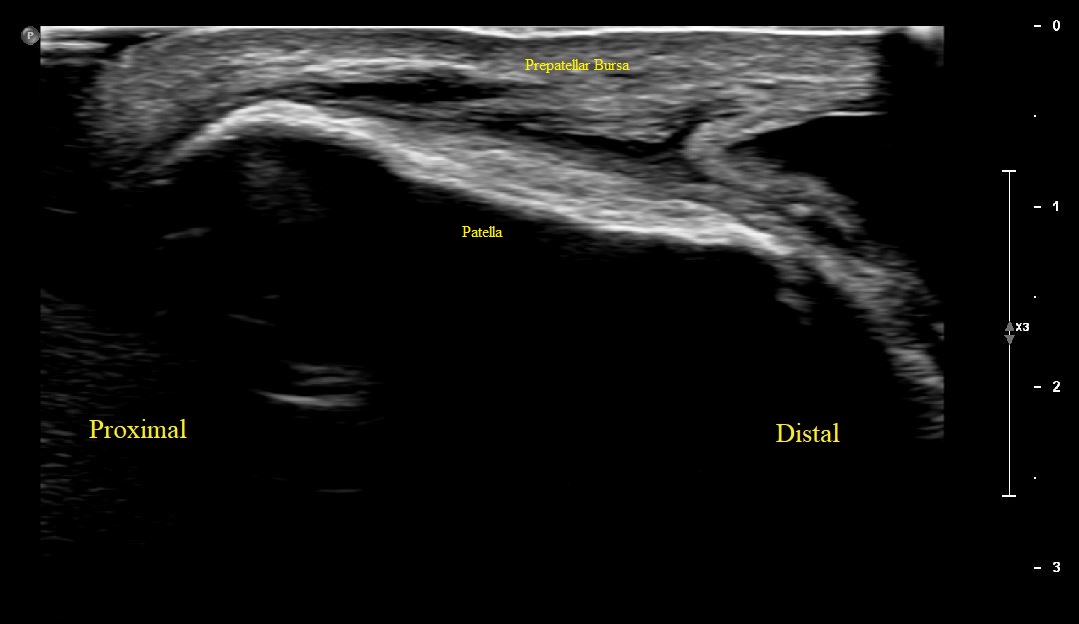

Long Axis view of Right Patella with overlying prepatellar bursal distension/bursitis. No fractures or cortical irregularities along patella.

Long Axis view of Right Patella with overlying prepatellar bursal distension.